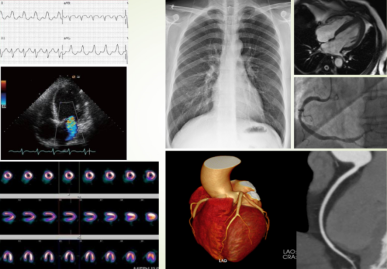

一、 冠状动脉粥样硬化性心脏病

(一)   (强调重点)影像学定义由动脉粥样硬化导致的至少1处冠状动脉管腔狭窄≥50%的心肌缺血性心脏病变。

1、冠状动脉CTA的临床价值课程的重点

1)       直接测量冠状动脉的直径判断狭窄程度;

2)       显示粥样斑块类型和部位;

3)       钙化积分的定量分析,反映病情发展,进行预测;

4)       冠状动脉支架及搭桥术后随访。

2、缺血性心肌病

1)       心肌缺血的类型

2)       CT表现:

a、    心室壁形态,密度,心室功能及心室血流的测定,来评价心肌缺血及其程度

b、    早期心室壁增厚,心肌梗死后变薄

c、    增强扫描:低密度区

d、    附壁血栓:充盈缺损

3)MRI的价值了解内容,鼓励自学,举手答疑。)